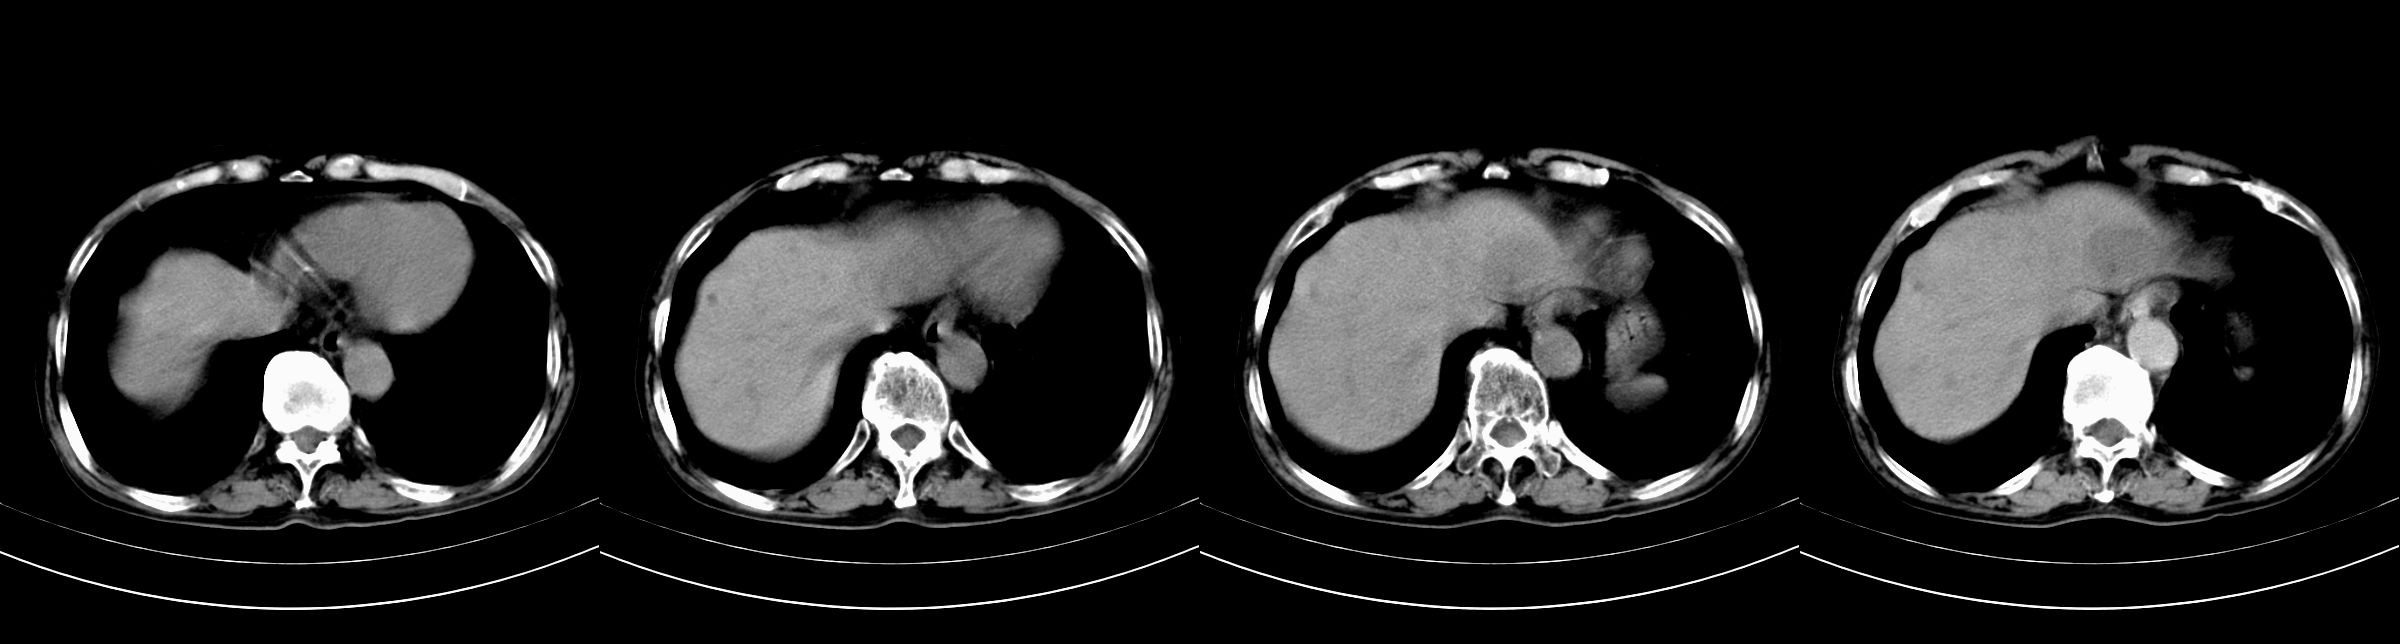

男,79y,无不适。体检发现肝脏占位。

肝内多发低密度结节,增强动脉期明显强化,门脉期逐渐下降,内有液化坏死区。

肝细胞癌(结节型)

鉴别:肝转移癌。

肝内多发低密度结节灶,增强动脉期明显不规则环状强化,;门脉期逐渐下降,肿瘤壁厚薄不一,内有坏死液化区。

诊断:肝转移癌可能

鉴别:1原发性肝癌(强化方式符合,建议查afp)

2肝脓肿(无临床病史支持)

诊断:典型的肝转移癌